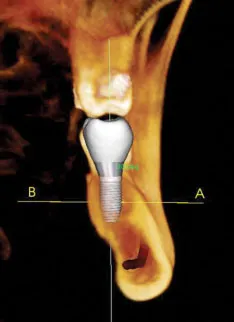

Here at Northwest Valley Oral Maxillofacial and Facial Cosmetic Surgery we are committed to excellence and providing innovative, high quality patient care. Because of this, our practice utilizes the state-of-the-art, full-cranial cone-beam CT (computed tomography) technology that provides highly accurate 3-D radiographic images.

Drs. Hammond or Haralson has direct access to advanced 3-D treatment tools for implants , restorations, oral and maxillofacial surgery, jaw reconstruction, and maxillary sinuses.

i-CAT produces high-definition 3-D diagnostic images for the ultimate treatment efficiency. Its push-button ease delivers maximum control to accurately capture each patient’s unique anatomy and treatment progress.

From diagnosis, through planning and treatment, to successful case completion, i-CAT’s flexibility allows Drs. Hammond or Haralson to select specifically desired scans and to manage radiation dose control for the greatest benefit to his patient’s.

i-CAT’s high resolution, volumetric images provide complete 3-D views for more thorough analysis of bone structure and tooth orientation. This allows Drs. Hammond or Haralson to collect precise data and measurements such as the concavity of the bone and the bone width and height. In the case of multiple implants, Drs. Hammond or Haralson is able to calculate a much more precise positioning of the implant.

This type of imaging allows us to obtain highly accurate information, in an office setting, that was never before thought to be possible. These 3-D radiographic images can obtain very pertinent information on the entire head and neck region. This allows for better diagnosis, better treatment planning, which in turn leads to better surgery. Undistorted, anatomically correct views of the jaws, teeth and facial bones are easily generated. Three-dimensional images enable a level of anatomical accuracy and patient care not possible with 2-D technologies.

Accurate and predictable treatment planning provides an increased level of confidence and extra margin of safety for our patients. We can achieve amazing results with 3-D treatment planning. This allows for the ideal placement of implants while taking into account both clinical and esthetical considerations. The CT guided surgery often allows for immediate loading of prefabricated prosthetics (teeth in a day).